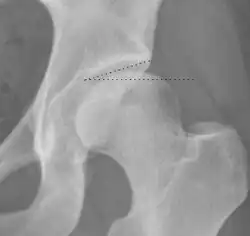

Radiograph of a pincer type impingement.